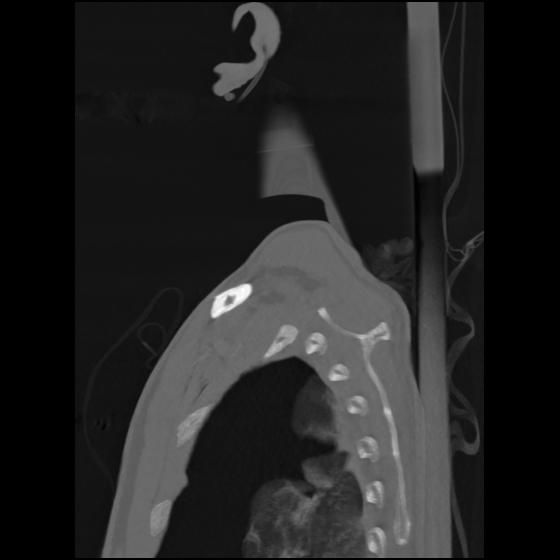

24 ANGIO,CE,Sag-MIP,5.000,ANGIO,Sag-MIP,